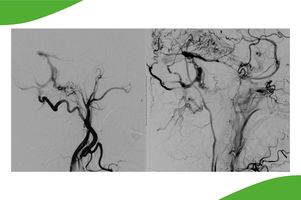

Eine Gehirnblutung kann unterschiedliche Ursachen haben, zum Beispiel ein Aneurysma oder Gefäßmissbildungen. Um zu differenzieren, aus welchem Grund eine Hirnblutung aufgetreten ist, wird eine Angiographie der vier gehirnversorgenden Gefäße durchgeführt.

Anhand dieser Untersuchung kann dann eine gezielte Behandlung geplant werden. Hier kommen neben der operativen Therapie durch die Neurochirurgie auch die interventionellen neuroradiologischen Verfahren mit sog. Coiling und Embolisieren in Betracht (siehe spezielle Behandlungsmethoden im Kopf-Halsbereich)